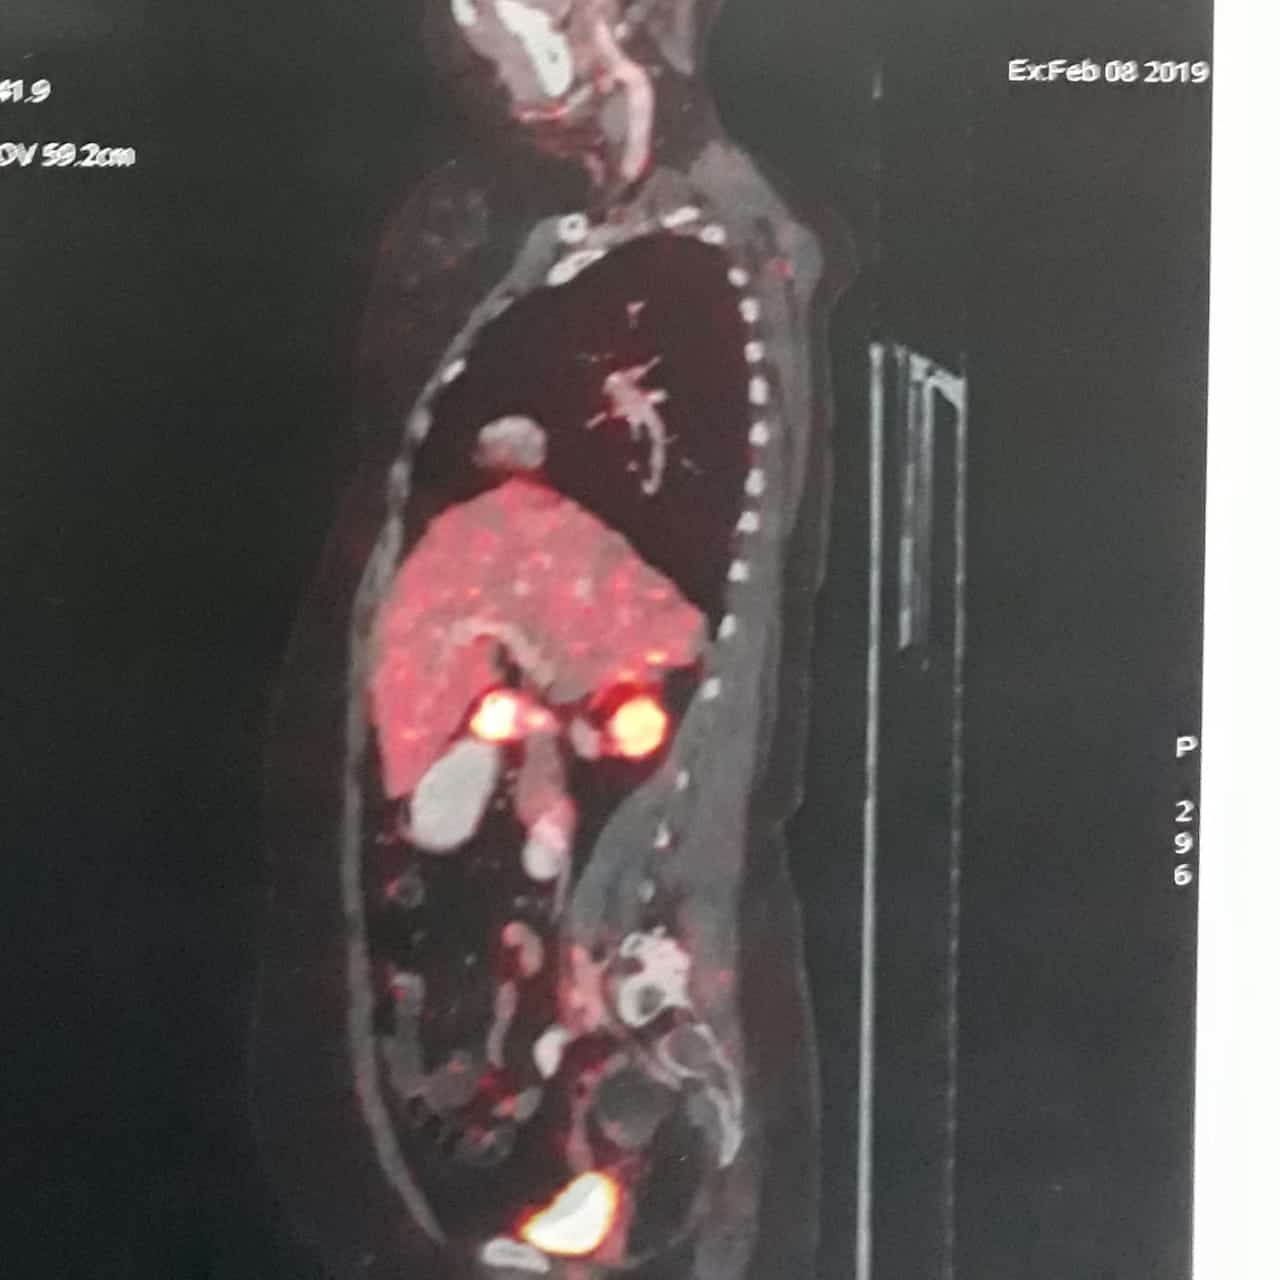

A Young lady who was a small kid...when her mother was operated for a Complex Gastrointestinal condition almost 14 years back by Dr Suddhasattwa Sen suddenly came in with severe blood loss from Gastrointestinal tract with a loss of almost 2 to 3 litres of blood with Shock with fainting . Further stabilisation was done and then extensive investigation revealed not only Piles and GI Ulcers but also SRUS Bleeding ulcers in rectum. A condition called Solitary Rectal Ulcer Syndrome ( a complex and difficult to cure anorectal problem ) . Her hemoglobin dropped to below 7 gm% She finally underwent surgery after 5 days and left home after 2 days post op without any further bleed or problems .